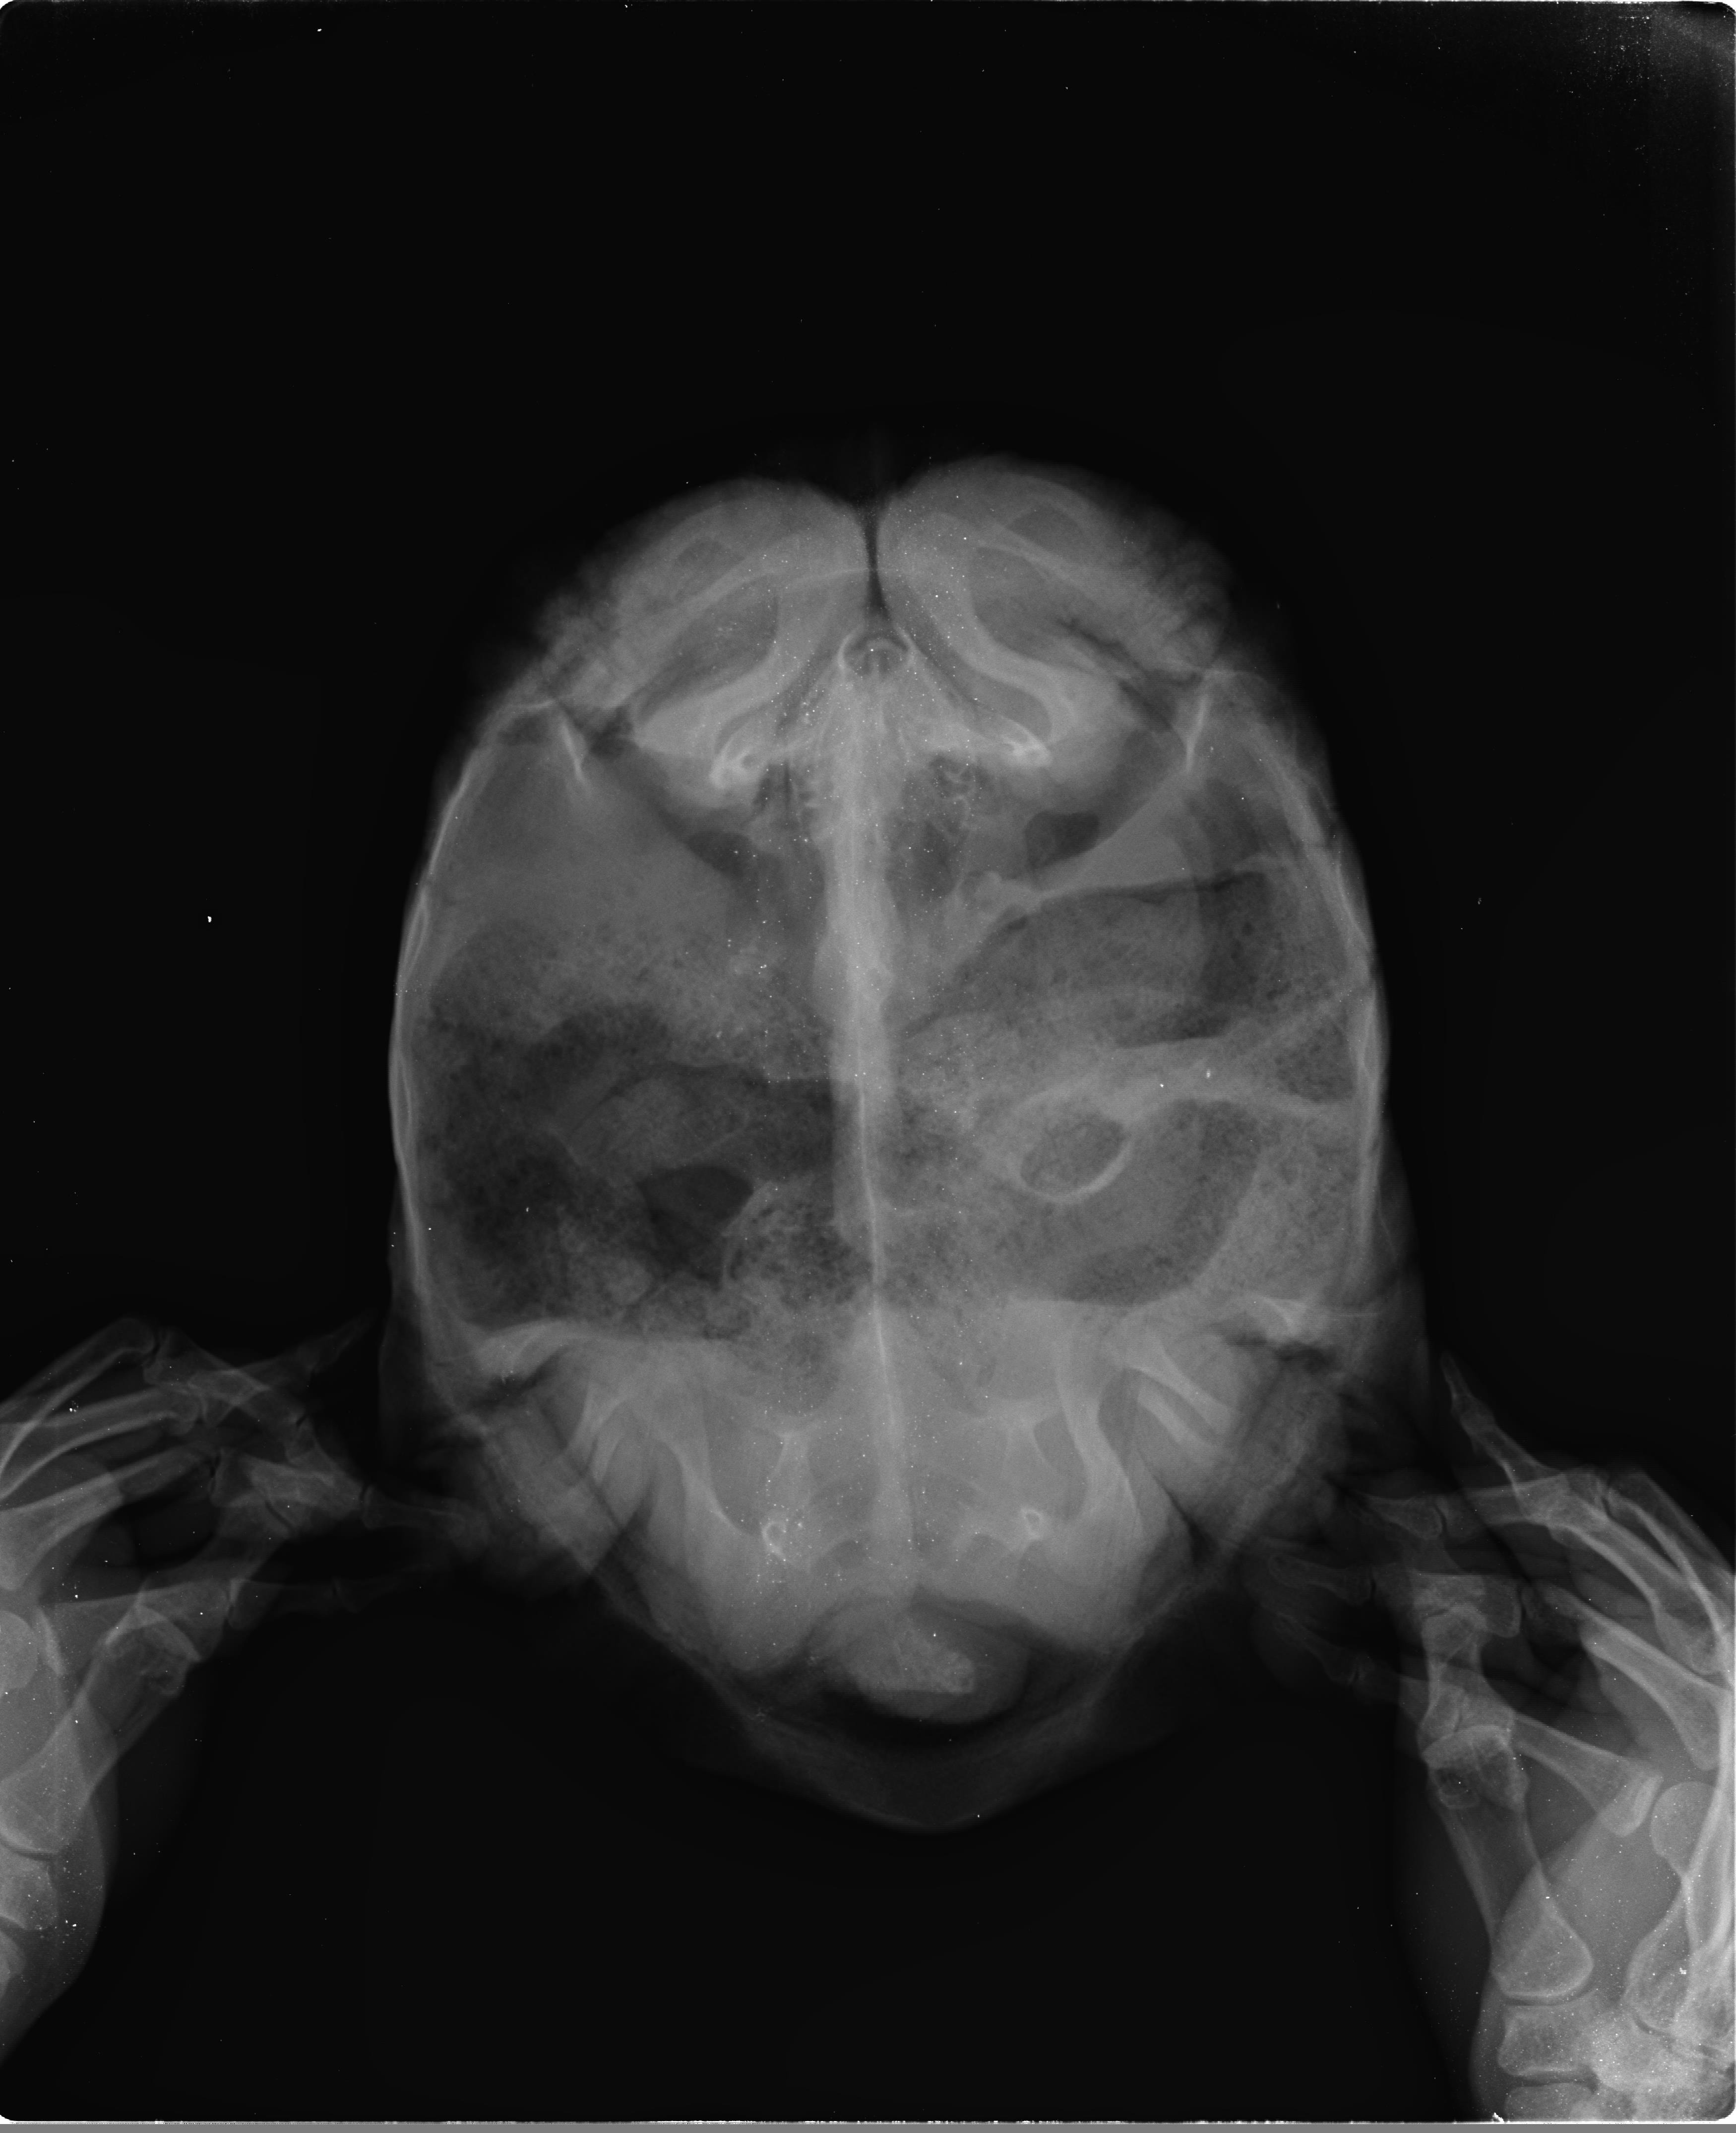

거북 X-Ray검사:정상(Normal)-레오파드거북 토르(11-08-2012, 2.6kg) 작성자가람캡틴|작성시간26.03.31|조회수2 목록 댓글 0 글자크기 작게가 글자크기 크게가 다음검색 현재 게시글 추가 기능 열기 북마크 공유하기 신고 센터로 신고 댓글 댓글 0 댓글쓰기 답글쓰기 댓글 리스트